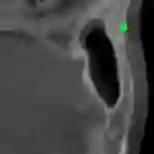

Detecting 3D landmarks on cone-beam computed tomography (CBCT) is crucial to assessing and quantifying the anatomical abnormalities in 3D cephalometric analysis. However, the current methods are time-consuming and suffer from large biases in landmark localization, leading to unreliable diagnosis results. In this work, we propose a novel Structure-Aware Long Short-Term Memory framework (SA-LSTM) for efficient and accurate 3D landmark detection. To reduce the computational burden, SA-LSTM is designed in two stages. It first locates the coarse landmarks via heatmap regression on a down-sampled CBCT volume and then progressively refines landmarks by attentive offset regression using high-resolution cropped patches. To boost accuracy, SA-LSTM captures global-local dependence among the cropping patches via self-attention. Specifically, a graph attention module implicitly encodes the landmark's global structure to rationalize the predicted position. Furthermore, a novel attention-gated module recursively filters irrelevant local features and maintains high-confident local predictions for aggregating the final result. Experiments show that our method significantly outperforms state-of-the-art methods in terms of efficiency and accuracy on an in-house dataset and a public dataset, achieving 1.64 mm and 2.37 mm average errors, respectively, and using only 0.5 seconds for inferring the whole CBCT volume of resolution 768*768*576. Moreover, all predicted landmarks are within 8 mm error, which is vital for acceptable cephalometric analysis.